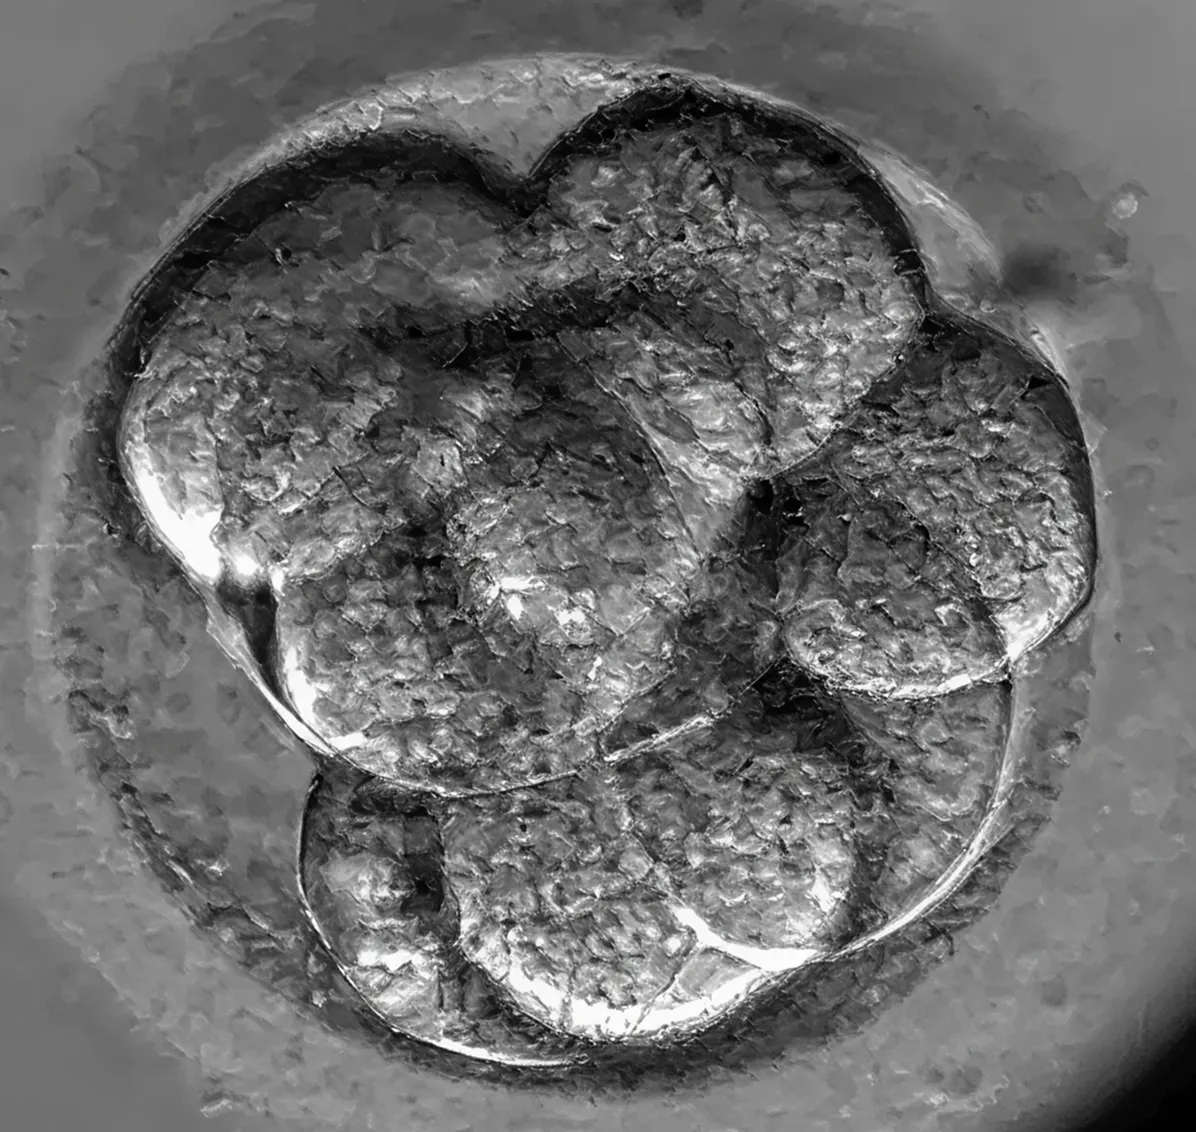

Първи клетъчни деления – зиготата (оплодената яйцеклетка) става ембрион

Зиготата започва да се дели – от една клетка стават 2, след това 4 – тези клетки се наричат бластомери. В този етап ембриолозите оценяват симетрията и качеството на клетките, както и наличието на фрагментация. В идеалния случай деленето е симетрично, т.е. бластомерите имат сходен размер и се делят синхронно – 2, 4, 8 и т.н. Неравномерното делене е често явление при човешките ембриони, като леката асиметрия не е непременно признак на лошо качество – много ембриони с неравномерни деления достигат до стадий бластоцист и водят до успешна бременност.

Какво се вижда? – голямата кръгла клетка се е разделила на 2, 3, 4, 5 или повече малки клетки, които все още са обградени от прозрачна обвивка – zona pellucida. Клетките не винаги са еднакви по размер и това е напълно нормално при човека.

Многоклетъчен ембрион

Ембрионът вече има около 8 клетки (бластомери). Това е моментът, в който клетките започват да си „говорят“ помежду си – да обменят сигнали и да се координират в развитието.

Какво се вижда? – Сега ще видите повече клетки – обикновено 7–9. Те вече започват да заемат различни позиции и понякога изглеждат неравномерни. Това е естествен процес, който подготвя ембриона за следващия етап.